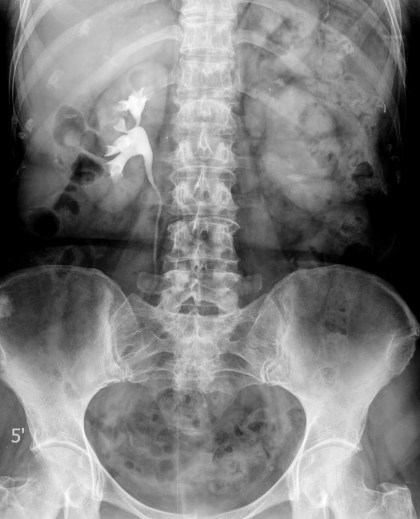

Radiografía simple y urografía intravenosa (UIV):

Es útil para localizar el calcio.

La realización de escopia con contraste es muy sensible, demostrando alteraciones en el 90% de los pacientes afectos.

- Cicatrices parenquimatosas.

- Estenosis infundibulares.

- Borrosidad (cáliz fantasma) o irregularidad de los cálices (apecto apolillado).

- Hidronefrosis.

- Dilataciones y estenosis del uréter (uréter arrosariado). El engrosamiento mural ureteral es mejor valorado en la TC.